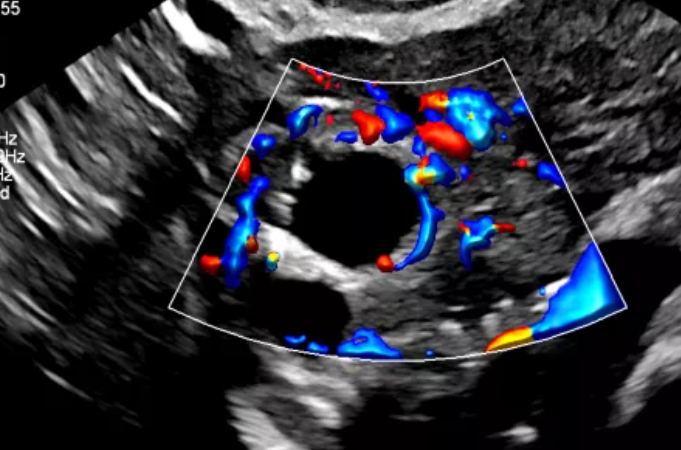

MicroFlow Imaging – мелкие сосуды в высоком разрешении

Специальная технология позволяет четко отображать на экране и снимках участки тканей с медленным или слабым кровотоком. Это очень ценно при исследованиях сосудов.

Благодаря использованию технологии специалисты получают:

- улучшенную визуализацию просветов;

- высокое разрешение в 2D и отличное качество получаемого изображения;

- минимальное количество артефактов при исследовании некрупных сосудов.

ЦДК перфузии яичника с Flow Viewer с датчиком C10-3v

MFI яичника, Flow Viewer

Кровоток в яичнике с MFI и датчиком C10-3v